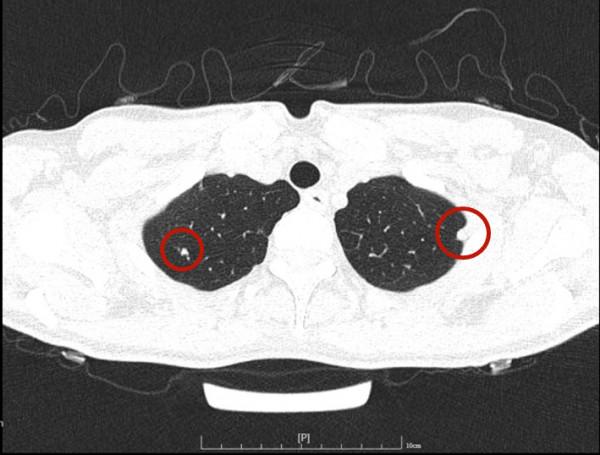

今天一位網路問診病人,女性,34歲,檢查發現雙肺多發實性結節,在當地醫院不同科室就診意見不一,再到不同醫院胸外科就診,意見也不一。怎麼辦呢?是結核、免疫疾病、風溼,還是腫瘤轉移?要不要手術活檢?我們來瞧瞧她的病例:

可見她體檢發現,沒有症狀,看了呼吸科、風溼免疫科、結核科以及胸外科,而且還看了三家三甲醫院的胸外科,但意見莫衷一是。其CT是如何的呢?來看看:

那麼多結節,基本上都是實性,分佈兩肺,形態不似圓形或類圓形的轉移瘤。是什麼呢?我們是不是一定要弄明白到底是什麼病?其實我覺得有時並不一定要弄清楚,所以我回復的意見如下:我認為我們看病,有時候可以從結果來反推,從而考慮是不是干預治療。比如這個病例的兩肺多髮結節,我看沒有一個是主病灶,也就是說“明顯考慮惡性的,其他考慮是這個病灶轉移的”這種樣子。那麼這些實性小結節,可能是:1、良性結節:包括慢性炎,纖維增生、肺內淋巴結、風溼結節、肉芽腫、隱球菌等各種可能性。但只要是良性,不處理不影響生命,也沒什麼不舒服,只需關注著,定期複查就可以了;2、腫瘤多發轉移:不管原發灶在哪裡,如果兩肺這麼多轉移,你再怎麼治療,預後也不好,現在還不是典型的腫瘤,也未見明顯的原發部位,遲點有進展再考慮又有多少區別呢?3、結核:即使真是結核,沒有明顯症狀的情況下,很多人自己得過結核也不自知,意思是說,如果痰找結核菌陰性,不是活動性肺結核,沒有症狀,不治療也沒什麼關係,也是隻需要定期複查。所以你的病例,我的意見是:1、形態數目不像惡性;2、不需深究到底是什麼;3、把診斷交給時間來決定,建議每4-6個月複查平掃,有變化時展再考慮活檢或干預,否則先不去管它。